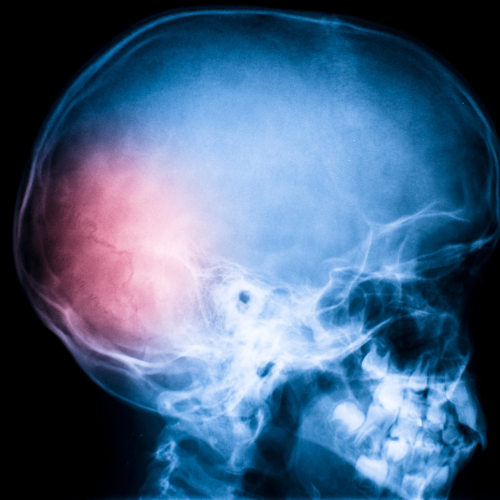

Omega-3 nuova potenziale terapia per il recupero dal trauma cranico

Pubblicati i risultati del primo studio che dimostra i benefici degli Omega 3 sul cervello durante la convalescenza che segue un trauma cranico. Gli Omega-3 potrebbero essere utili per ridurre gli effetti negativi a lungo termine sul cervello di un trauma cranico. In particolare, secondo gli esperti gli effetti maggiori si potrebbero ottenere somministrando al paziente questi acidi grassi già al pronto soccorso. A suggerirlo sono Michael Lewis, Parviz Ghassemi e Joseph Hibbeln, autori di uno studio pubblicato sull'American Journal of Emergency Medicine1 in cui, per la prima volta, sono stati testati gli effetti della somministrazione di Omega-3 durante la convalescenza dopo un trauma cranico.

Negli ultimi anni è aumentato anche l'interesse nei confronti dei potenziali benefici esercitati da questi nutrienti in seguito a trauma cranico, una delle cause principali di morte traumatica e di disabilità. La mortalità associata a questo tipo di trauma si è molto ridotta grazie all'avanzamento delle metodiche chirurgiche e di terapia intensiva, ma non esistono ancora terapie specifiche per affrontare la fase di convalescenza. Il recupero passa, infatti, attraverso un periodo in cui il cervello deve fare i conti con problemi come l'infiammazione e la presenza di radicali liberi. Nel 2010 l'Istituto di Medicina degli Stati Uniti (IOM) ha indicato proprio gli Omega-3 fra le molecole di cui dovrebbero essere testati i benefici in questa fase di convalescenza e lo studio di Lewis e colleghi è il primo a cercare di gettar luce su queste potenzialità. I ricercatori hanno somministrato a un adolescente reduce da un grave incidente motociclistico dosi elevate di questi acidi grassi. In particolare, 10 giorni dopo il trauma cranico il ragazzo ha ricevuto 9,756 grammi di EPA (acido eicosapentaenoico) e 6,756 grammi di DHA (acido docosaesaenoico), i principali Omega-3 di origine alimentare. La terapia, hanno spiegato gli autori, ha permesso graduali miglioramenti sia dal punto di vista cognitivo, sia da quello fisico, tanto che a 3 mesi di distanza dall'incidente il ragazzo si è diplomato e 4 mesi dopo il trauma ha potuto far ritorno a casa, dove ha continuato la terapia per tutto l'anno successivo.